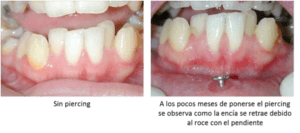

ntes en las consultas odontológicas. Estas personas deberían realizar un seguimiento más exhaustivo de su salud oral, ya que el piercing puede derivar en algunas complicaciones.

ntes en las consultas odontológicas. Estas personas deberían realizar un seguimiento más exhaustivo de su salud oral, ya que el piercing puede derivar en algunas complicaciones.